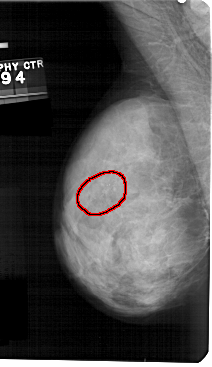

A_1326_1.LEFT_MLO

LEFT_MLO LINES 5491 PIXELS_PER_LINE 3166 BITS_PER_PIXEL 12 RESOLUTION 43.5 OVERLAY

FILE: A_1326_1.LEFT_MLO.OVERLAY

TOTAL_ABNORMALITIES 1

ABNORMALITY 1

LESION_TYPE CALCIFICATION TYPE PLEOMORPHIC DISTRIBUTION LINEAR

ASSESSMENT 4

SUBTLETY 4

PATHOLOGY BENIGN

TOTAL_OUTLINES 1

BOUNDARY